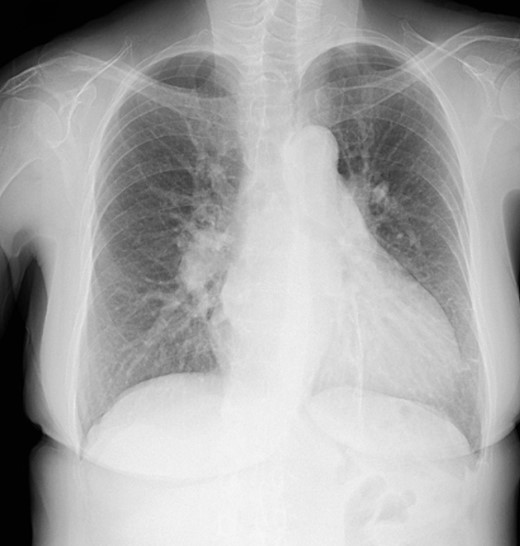

The patient had an uneventful postoperative course during her hospital stay. Echocardiography on postoperative Day 8 showed an EF of 64%, trivial MR, a mean PAP of 18 mmHg, and no shunt flow (Fig. 4). Therefore, the patient was discharged on the 19th day after surgery. The patient is doing very well 7 months after surgery.

Postoperative cardio echography showing an EF of 64%, trivial MR, mean PAP of 18 mmHg, and no shunt flow.